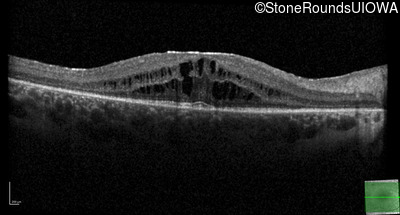

Optical Coherence Tomography - Left - 20/32 -1

Exemplar / OCT Stack

OCT Stack